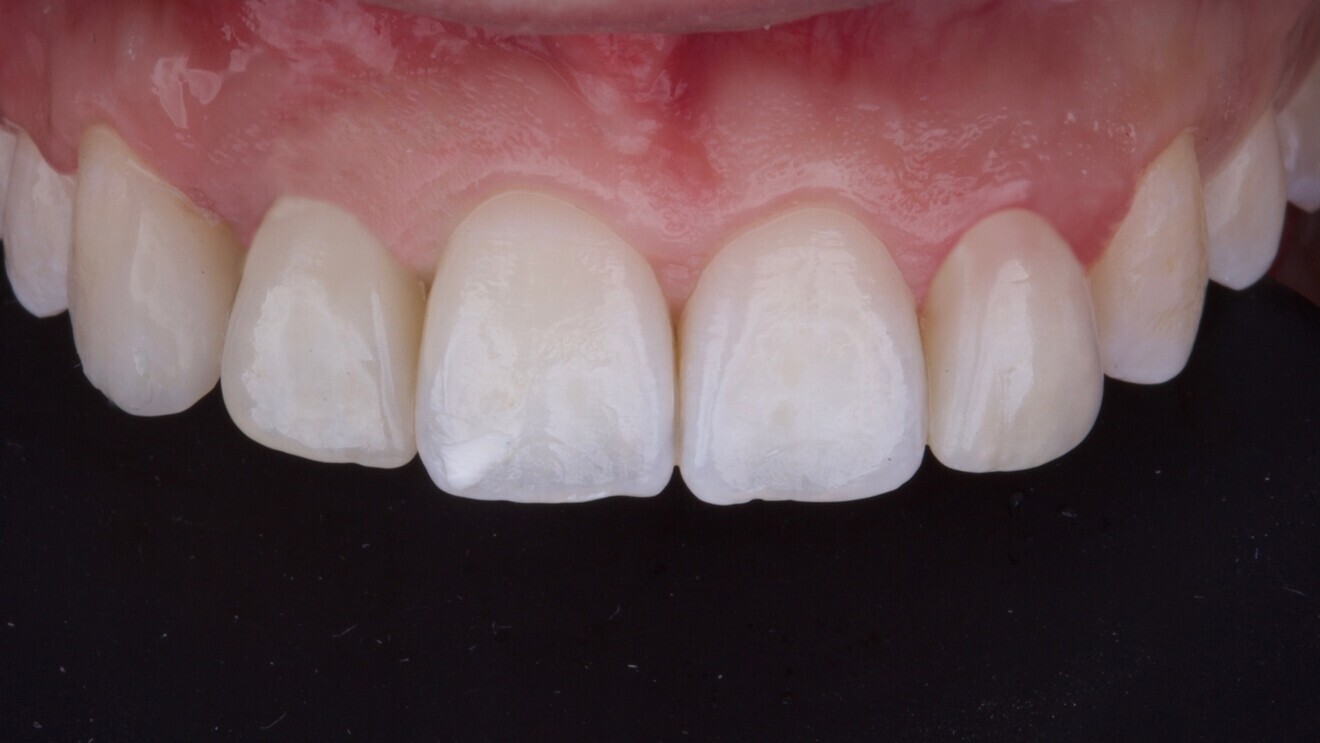

Fig. 1: Peri-implant mucosal inflammation and umbrella effect from bone loss and titanium show-through. (All images: Dr Marco Tallarico)

A 26-year-old partially edentulous female patient was referred to our clinic with an aesthetic concern in the region of the maxillary right lateral incisor. Clinical examination revealed an osseointegrated but malpositioned implant. The peri-implant soft tissue appeared thin and inflamed. Additionally, a dark-greyish discoloration was visible through the gingiva—referred to as the umbrella effect—caused by the loss of peri-implant bone and show-through of the titanium implant (Fig. 1).